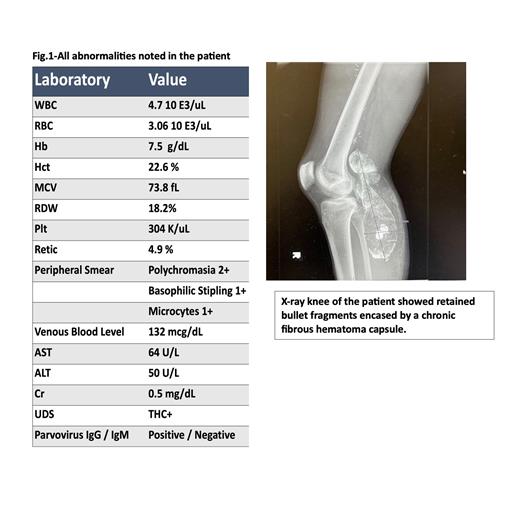

A 19-year-old Hispanic male presented to the emergency department with symptoms of worsening abdominal pain, anorexia, weight loss (10 lbs. over 2 months), constipation, low back pain, right knee pain, and headache that has been going on for two weeks. Complete blood counts showed microcytic anemia with a peripheral smear showing basophilic stippling; Computerized tomography of the head, abdomen, and pelvis showed no acute findings. Iron profile was within normal limits. Upon careful history and examination, he revealed that he had suffered an accidental gunshot injury to his right knee 6 years ago with retained bullet and had undergone a popliteal artery repair. His knee ray showed retained bullet fragment encased in a chronic calcified hematoma. This led us to suspect lead poisoning and ordering of venous lead level. His blood lead level came back and was elevated to a toxic level of 136.2 mcg/dl (Normal <5.0 mcg/dl).